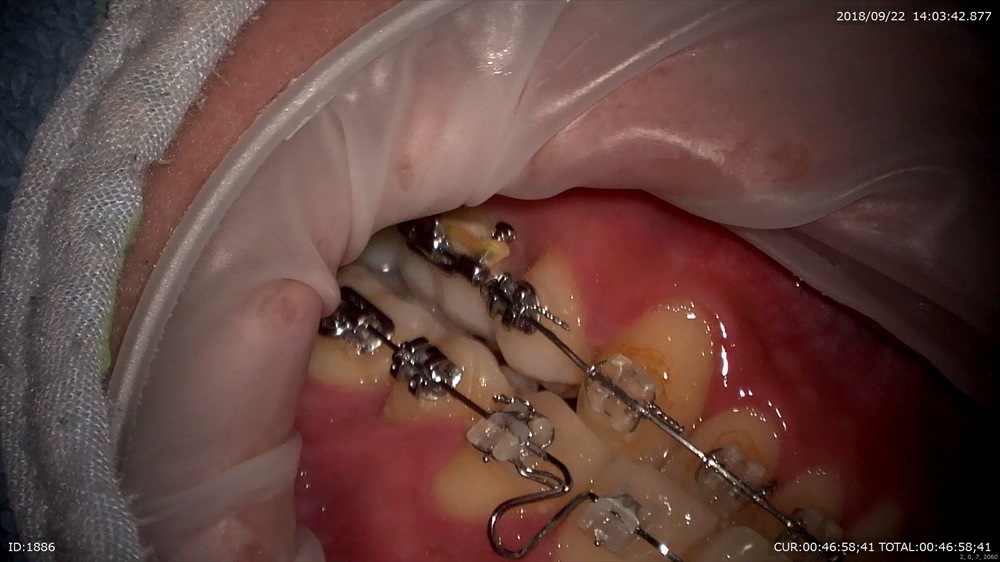

本日矯正を外す日

装置除去。ガタガタの歯並びは綺麗になりました。2年かかりました。抜歯症例。

マイクロスコープ下でボンディング

EXTARO300ここまで広範囲に。しかも直視で上顎が見えます。これマイクロを使用している先生がみたら私の言いたい事が解ると思います。